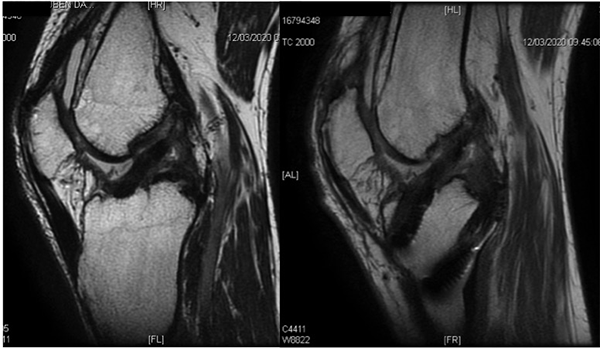

Figura 11: RM (cortes sagitales secuencia T1) de control a los cuatro meses de la reconstrucción artroscópica del LCA/LCP simple banda. Se observa ubicación anatómica de túneles. Injertos continuos en posición anatómica con intensidad heterogénea compatible con tiempo quirúrgico. Señal homogénea de tendón cuadricipital remanente sobre el aparato extensor.